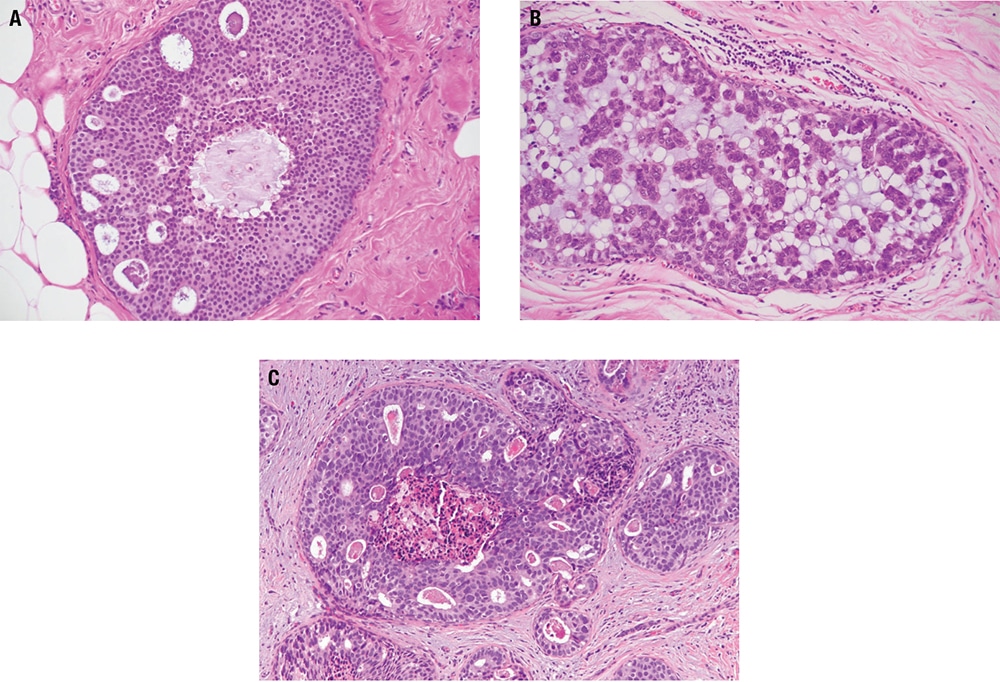

Prototypical morphology

- There are expanded terminal duct-lobular units in a pattern similar to blunt duct adenosis/columnar cell alteration; however, the luminal spaces tend to be more rigid and round.

- As in blunt duct adenosis/columnar cell alteration, the cells may be columnar or cuboidal, and apical cytoplasmic snouts and luminal calcifications are often present.

- The luminal cells (Figure 5-8) are monomorphic, contain small nucleoli, and have nuclei that are enlarged, rounded, and without polarity; these are the main features that distinguish FEA from blunt duct adenosis/columnar cell alteration, and these are the features that it has in common with ADH/DCIS.

- The epithelial proliferation is flat (it may be pseudostratified but is not stratified), with no architectural complexity or bridging, in contrast to ADH/DCIS.

- Careful evaluation of adjacent foci for atypical lobular hyperplasia, ADH, and DCIS is recommended.

Special studies - The luminal cells are strongly positive for ER and Bcl-2.

Prototypical morphology

- ADH is an intraductal proliferation (Figure 5-9) in which the qualitative morphologic features of low-grade DCIS are present focally.

- Ducts are mildly expanded, and there is architectural complexity with punched-out cribriform spaces, micropapillae, or rigid arched bridges.

- The cells are low grade and monomorphic with round nuclei, condensed chromatin and inconspicuous nucleoli (intermediate or high nuclear grade, regardless of quantitative extent, are characteristics of DCIS).

- The atypical proliferation involves less than 2 mm extent or less than two contiguous ducts (greater than 2 mm or two contiguous ducts characterized as DCIS).

Prototypical morphology

- The lobule is expanded (Figure 5-11), and acini are filled with small, loosely cohesive monomorphic cells (classic type), by definition in greater than 50% of a terminal duct lobular unit.

- When involving ducts, the neoplastic cells proliferate between basement membrane and luminal epithelial cells in a clover leaf-like pattern.

- Pleomorphic LCIS shows increased nuclear pleomorphism and atypia, sometimes with central necrosis and calcification, closely resembling DCIS.

- Florid LCIS shows classic nuclear features but fills and distends ducts in a DCIS-like pattern, often with comedonecrosis.

Prototypical morphology

- Grossly, most cases demonstrate no apparent lesion. There may be cheesy material identified within dilated spaces in comedo-type DCIS, and in other cases there may be an indurated lesion.

- DCIS can be low, intermediate, or high grade (Figure 5-12). Grading is based largely upon nuclear features, but some grading systems take necrosis into account.

- Architectural patterns include solid, cribriform (with rigid punched-out spaces), comedo, papillary, micropapillary, clinging, etc, but these are often mixed, and reproducibility is poor.

- Necrosis must be distinguished from luminal secretion, which lacks evidence of cell death and instead consists solely of acellular eosinophilic granular material. Sometimes necrosis occurs in the center of a duct involved by solid-type DCIS, and this is called comedonecrosis. In other cases, central necrosis is present with cribriform or other patterns, while in still other cases necrosis may involve random individual cells (“punctate” necrosis).

- Low-grade DCIS is by definition greater than 2 mm or involves more than two contiguous ducts, while there is not a quantitative criterion attached to high-grade DCIS.

- Extensive high-grade DCIS may be associated with foci of microinvasion.